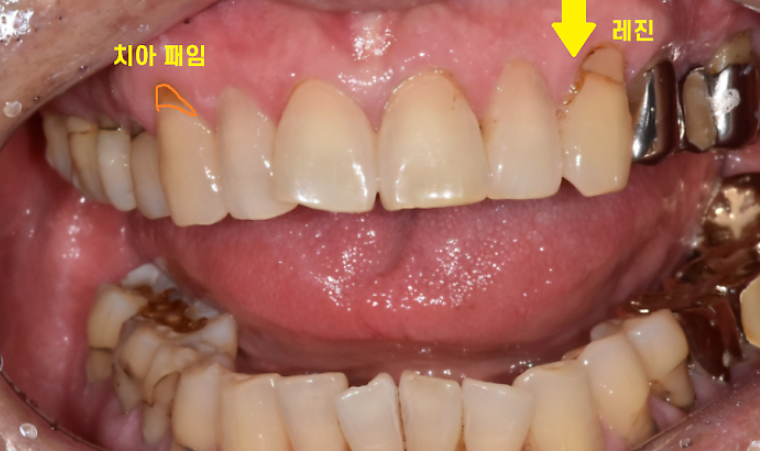

사진에서 보시는 것처럼 아주 작은 충치(점상 충치)는 상대적으로 간단하지만, 범위가 넓거나 앞니처럼 심미성을 크게 고려해야 하는 부위는 치료 시간이 2배 이상 걸리기도 합니다.

치아 목 부분 마모증 레진 치료 전후 비교 사례